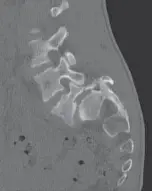

- التصوير بالرنين المغناطيسي (MRI): هو المعيار الذهبي لتشخيص الانزلاق الغضروفي. يوفر صوراً مفصلة للأنسجة الرخوة مثل الأقراص الفقرية والأعصاب والحبل الشوكي، ويُظهر بوضوح مكان وحجم الانزلاق ومدى تأثيره على الأعصاب.

- الأشعة السينية (X-ray): تُستخدم لتقييم استقامة العمود الفقري، والبحث عن علامات التغيرات التنكسية أو كسور الفقرات، على الرغم من أنها لا تُظهر الأقراص الغضروفية مباشرة.

- التصوير المقطعي المحوسب (CT Scan): قد يُستخدم في بعض الحالات لتقييم العظام بشكل أفضل، خاصة إذا كان الرنين المغناطيسي غير ممكن.

- الأشعة السينية (X-ray): تُظهر الأشعة السينية مع مناظر جانبية ومائلة (Oblique Views) عيب البرزخ (كسر سكوتي الكلب) والانزلاق بوضوح. كما تُستخدم أشعة ديناميكية (Dynamic X-rays) (ثني وتمديد) لتقييم استقرار العمود الفقري ومقدار الانزلاق مع الحركة.

- التصوير المقطعي المحوسب (CT Scan): يوفر صوراً مفصلة ثلاثية الأبعاد للعظم، وهو الأفضل لتحديد موقع وخصائص كسر البرزخ.

- التصوير بالرنين المغناطيسي (MRI): مفيد لتقييم الأنسجة الرخوة مثل الأعصاب والأقراص، وتحديد مدى تأثير الانزلاق على الحبل الشوكي أو جذور الأعصاب.